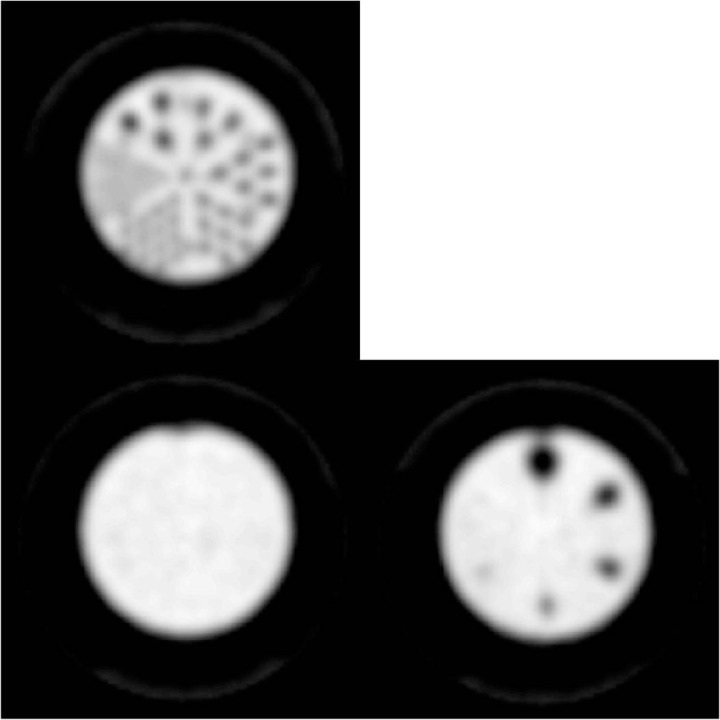

Figure 7.

Comparison of attenuation correction methods. Left: Rod (top) and uniform (bottom) sections of the phantom with attenuation derived from a CT scan of the phantom. Right: Rod (top) and uniform (bottom) sections of the phantom with attenuation derived from a model of the Small Phantom that is preloaded in the scanner software.